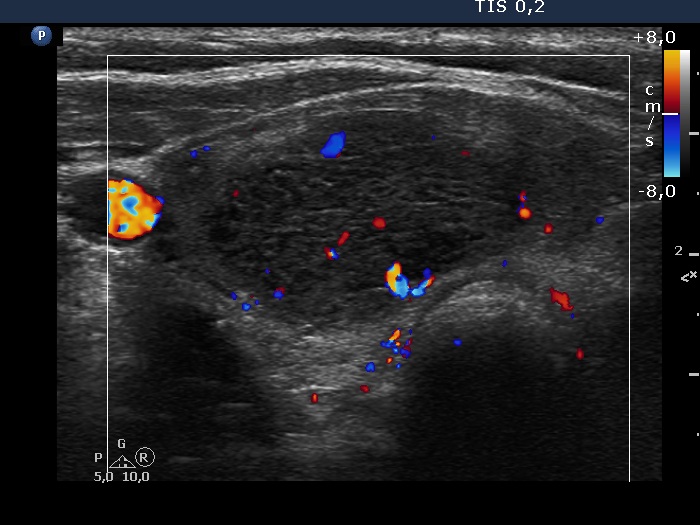

Follow-up investigation 3 years later (ultrasonographic picture 6)

Lower part of the right lobe, transverse scan, color Doppler mode. The vascularity is average.